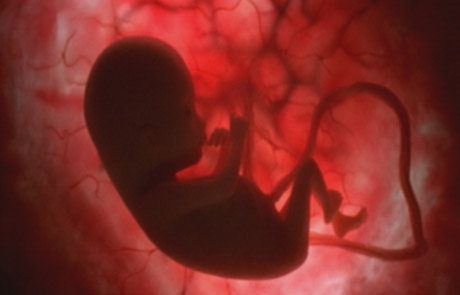

He recuperado la galería de fotos de en el vientre materno de mi vieja web. Como os dije en el artículo anterior, estoy en el momento oportuno para ver con detalle estas fotografías sobre la gestación. Podeis descargar las fotos aquí o ver la galería a continuación

También podeis ver la galería con comentarios a pie de cada fotografía en el diario 20minutos

Adicionalmente y aunque no sean las de National Geographic teneis otra galería de fotos sobre la gestación titulada La Vida en el Vientre Materno

Por cierto, que flipe la antepenúltima foto. Se le ve toda la carita perfectamente ¿Vosotros os hicisteis la 3D? Tiene que ser impresionante ver la cara de tu bebé antes de que nazca

Gracias Jmarior por estas fotos.

Son impresionantes!

me parece una exelente pagina porque nos enseña a conocer cosas que no sabemos